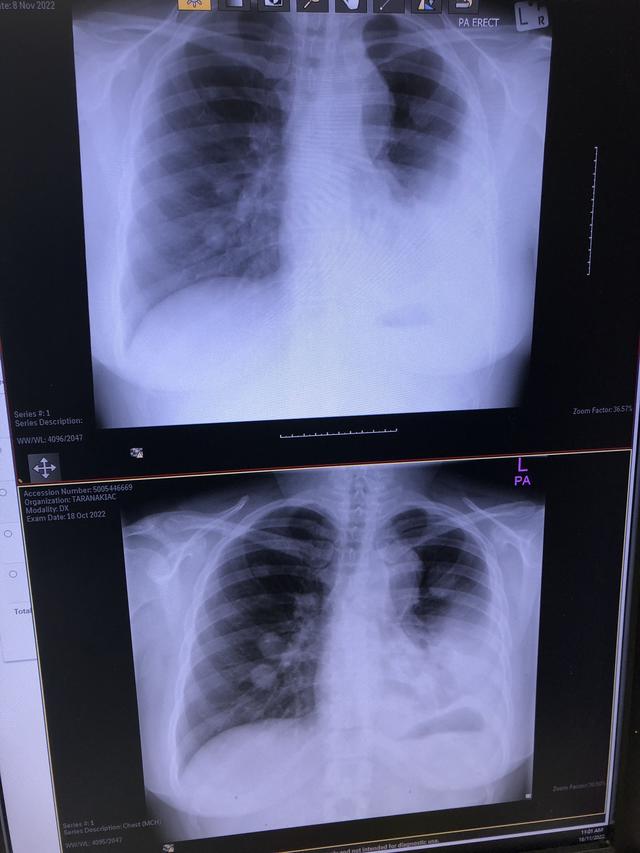

Main image

Just an update for those following my journey

Top scan was last week

Bottom scan was 3 weeks prior

Some shrinkage seen in the nodules 🙌

Some fluid in lungs but managing ok with that

Much more hopeful than weeks ago and thinking positive ❤️💗🌸